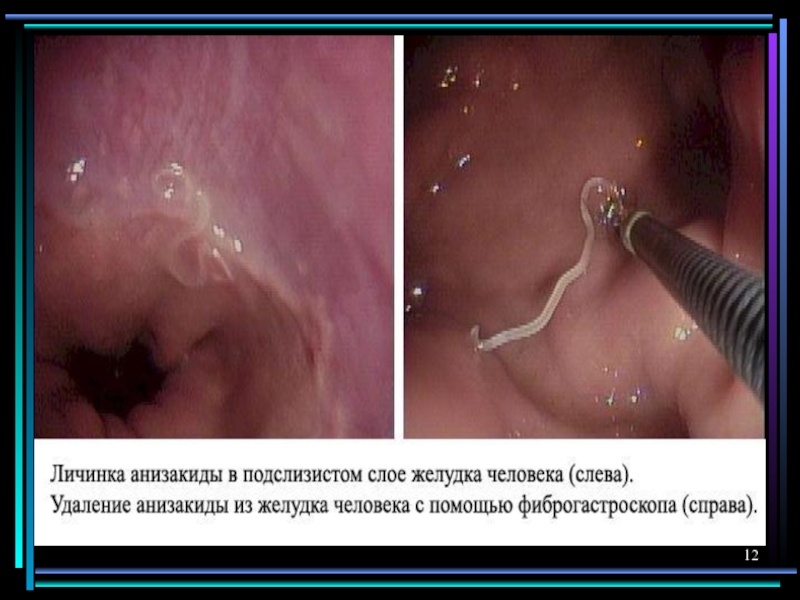

Анизакидоз

Язвенный гастродуоденит, анемия